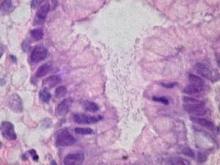

“I’m convinced we’re going to find a huge amount of information" about chronic diseases and infections, she concluded in a featured talk at the meeting. She speculated on and offered some evidence for a role of microbes in a variety of chronic conditions, like cancers, vascular disease, cystic fibrosis, and obesity. It’s an understandable view from a researcher who, nearly 2 decades ago, came to medical prominence by leading a group of researchers who found good evidence that gastric infection by Helicobacter pylori linked to the development of gastric mucosa-associated lymphoid tissue (MALT) lymphomas. She also noted that the pathogen-chronic pathology idea didn’t start with her, citing a 2000 book, Plague Time by Paul W. Ewald, that posited the same notion.

Last month, she focused on a possible role for H. Pylori and other gut flora in obesity. “H. pylori seems to affect appetite, and what you want to eat,” she noted, while “other chronic infections, like Giardia, can affect what’s absorbed” through the GI tract. “Gut flora can affect what you feel like eating, what gets absorbed, and basal metabolic rate,” she noted. “Weight is very complicated, but I guarantee that infection plays a strong role in what happens with it.”

Perhaps, or her theory could be dismissed as speculation. Except the next day at the meeting researchers from Columbia University in New York, who had nothing to do with Dr. Parsonnet, reported suggestive evidence linking past exposure to H. pylori and new-onset diabetes. Data from a prospective study of 790 Latino Americans more than 60 years old and living in the Sacramento area showed people with positive serology for H. pylori had a greater than two-fold risk for later developing diabetes. In a multivariate analysis that controlled for a list of potential confounders, study participants who were seropositive for H. pylori at baseline had a statistically significant, 2.7-fold increased rate of incident diabetes during more than 8 years of follow-up, reported Dr. Christie Y. Jeon, a researcher at Columbia.

The link between H. pylori seropositivity and diabetes did not seem related to inflammation or insulin resistance. Her best guess at what links the two was that gut microbiota cause changes in nutrient metabolism, energy harvesting, or gene expression, she said. But the association she reported provides only a hint, if for no other reason that the H. pylori marker Dr. Jeon relied on was seropositivity, a sign of exposure sometime during the subject’s lifespan, without evidence for a recent, active infection.